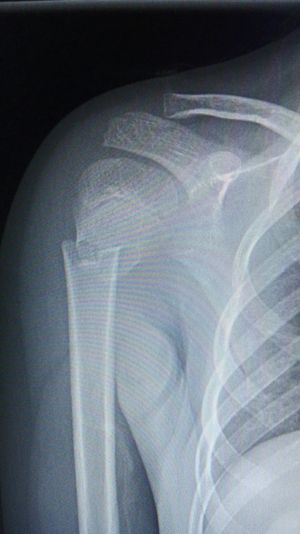

Xray

Fracture

Child

Shoulder